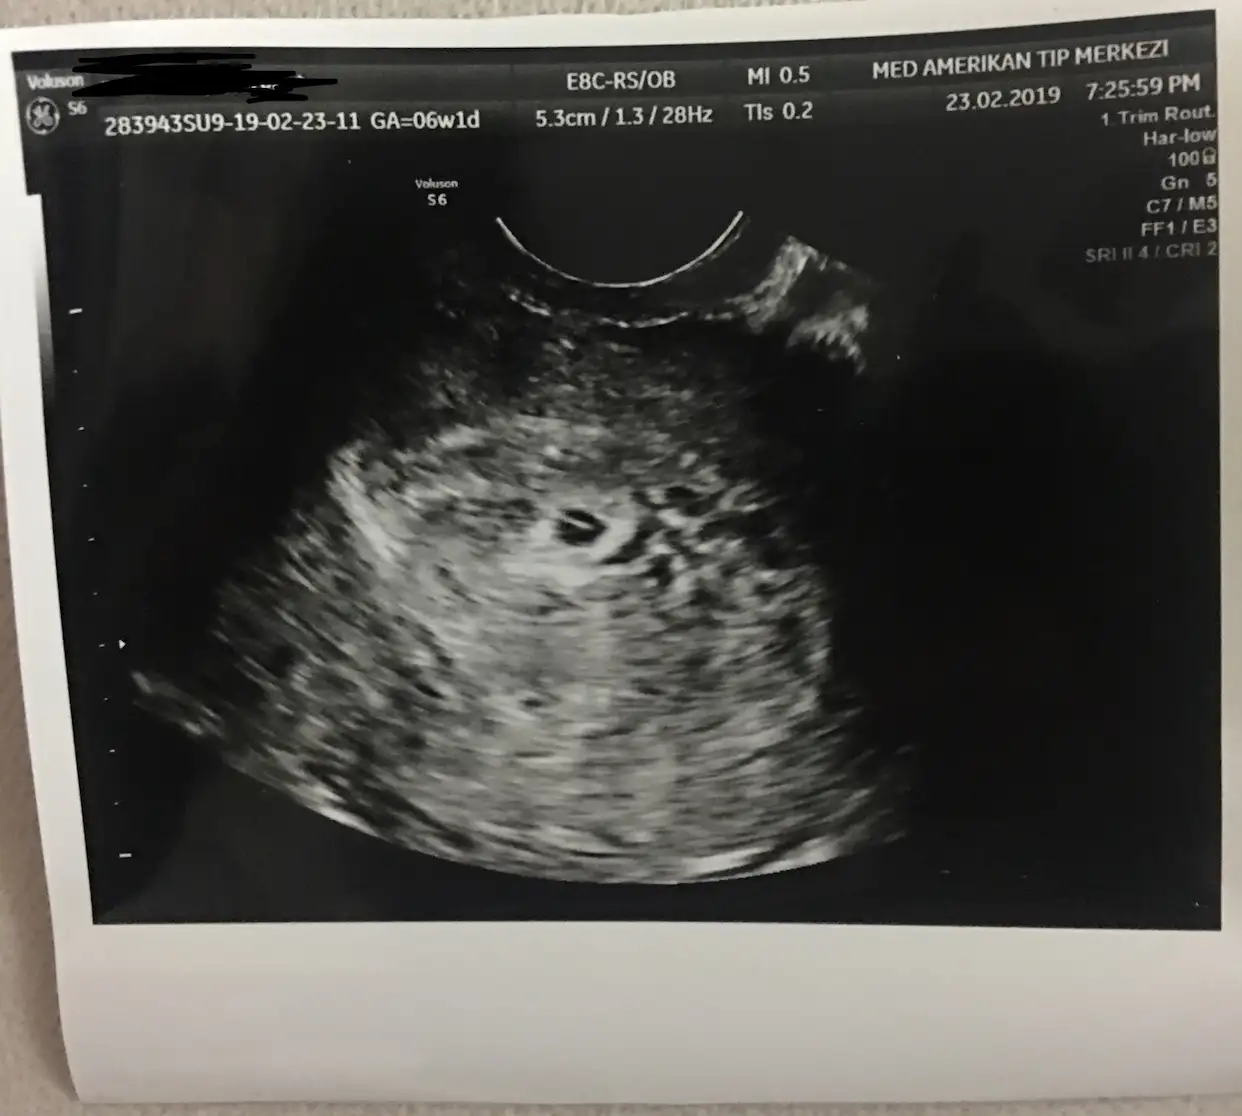

Bu da ultrason görüntüsü, anlayan varsa yazsın lütfen :))

Canim hah uste ayni durum beyaz kese yuvarlak.. icinde siyahlik icinde kucuk beyaz bisey vardi ortasinda.. bu bebek mi dedim yok artik daha degil ilsa olsa o daha yolk sac dedi ama gordum yani icinde beyazlik vardi.. senin kavinci haftaydi?Kesenin içinde beyaz bişey vardı bu bebek oluşmaya başlamış demek dedi, ama tüp bebek doktoru olduğu için mi yoksa kese çok küçük olduğu için mi detaylı konuşmadı bilmiyorum haftaya eski doktoruma da mı gitsem diye düşünüyorum açıkçası :) senin keseyi ölçmüş müydü doktor ?